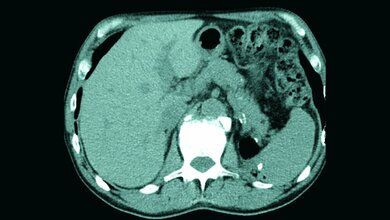

Schlüsselwörter: Persistierende Chorda dorsalis, Röntgen, CT, MRT

Keywords: Persist chorda dorsalis, x-ray, CT, MRI